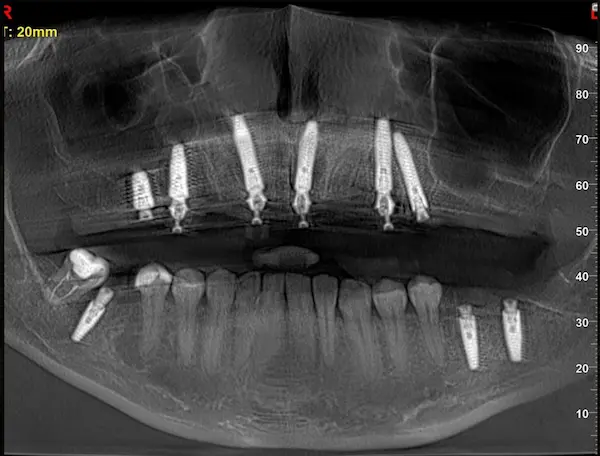

Сканы КТ имплантации зубов, 2026-04-18

Скан КТ, 2026-04-18

Сканы КТ имплантации зубов, 2026-04-18

Скан КТ имплантации зубов, 2026-04-17

Сканы КТ имплантации зубов, 2026-04-18

KT: имплантация зубов DentalKnysh, 2025-01-03, сканы

KT: имплантация зубов DentalKnysh, 2025-01-03, сканы

KT: имплантация зубов DentalKnysh, 2025-01-03, сканы

КТ имплантации зубов в DentalKnysh (10 имплантов), 2023-11-03

С 2023-09-05 по 2023-09-09 сканы КТ от 6 до 12 имплантов в DentalKnysh (4 фото):

Синуслифтинг и имплантация зубов, 6 имплантов, all-on-6, КТ скан 1, 2023-08-31

Фото отчет Имплантация зубов, 6 имплантов, КТ скан 3, 2023-08-31

Фото отчет Имплантация зубов, 8 имплантов, all-on-4, КТ скан 1, 2023-08-31